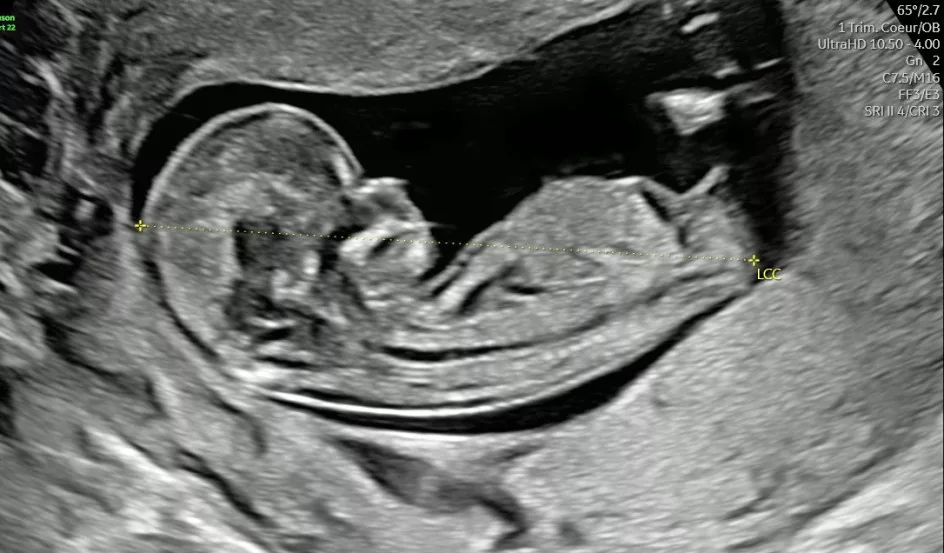

​L’image du fœtus est obtenue après un traitement informatique de la propagation à travers les tissus maternels des ultrasons émis et recueillis par la sonde d’échographie.

L’image du fœtus peut être obtenue soit à travers la paroi abdominale maternelle, soit à travers sa paroi vaginale.

Il s’agit d’une image virtuelle, correspondant à une réalité transformée par les ultrasons et le traitement informatique de l’image. L’échographe n’est pas une caméra, et ne permet pas de « voir le bébé ».

1. Au premier trimestre : Pour être considéré comme valide en tant qu’examen habituel de dépistage du premier trimestre, l’examen doit avoir été réalisé de sorte que la valeur de longueur crânio-caudale (LCC) soit comprise entre 45 et 84 millimètres. Ses principaux objectifs sont la datation du début de grossesse, l’identification et la caractérisation des grossesses multiples, l’évaluation du risque d’anomalie chromosomique et le dépistage de certaines pathologies.